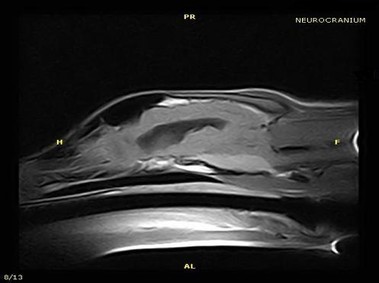

В настоящее время МРТ является наиболее предпочтительным методом визуализации любых мягких тканей, особенно для визуализации травм и патологий центральной нервной системы и суставов. Особенности Vet-MR позволяют использовать данный метод визуализации также в сфере ветеринарии.

Vet-MR специально разработана для визуализации небольших животных и является результатом внимания к деталям при разработке магнита, катушки и электронных компонентов, обеспечивая высокое качество экономически эффективной и простой в использовании МРТ в сфере ветеринарии.